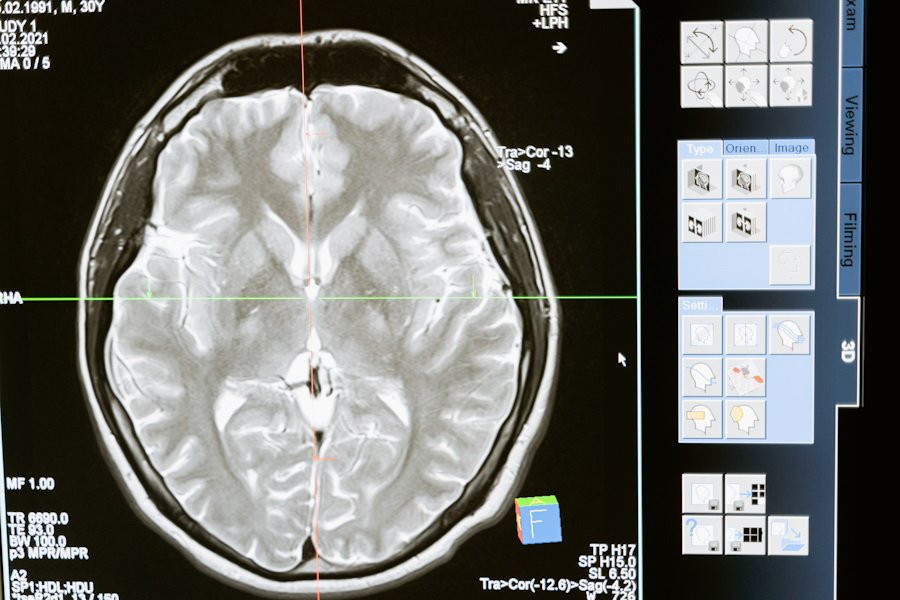

Фото из открытых источников

Исследователи из Institute for Basic Science (IBS) (Республика Корея) провели успешные испытания новой методики Magnetogenetic Interface for NeuroDynamics (Nano-MIND), которая позволяет воздействовать на мозг человека без использования имплантатов. Эта технология объединяет магнитные поля и намагниченные наночастицы, что открывает новые возможности для нейромодуляции, сообщает портал Nature.